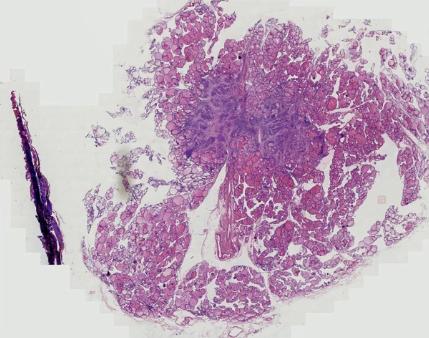

结果显示佟女士的 甲状腺体积增大,包膜欠完整 ,双侧叶可见多个囊实性及等回声结节,边界欠清,部分结节相互融合。

右侧叶最大者 23mm*16mm ,左侧叶最大者 39mm*23cm , TI-RADS 3类,弹性评分2分,良性结节的可能性比较大。